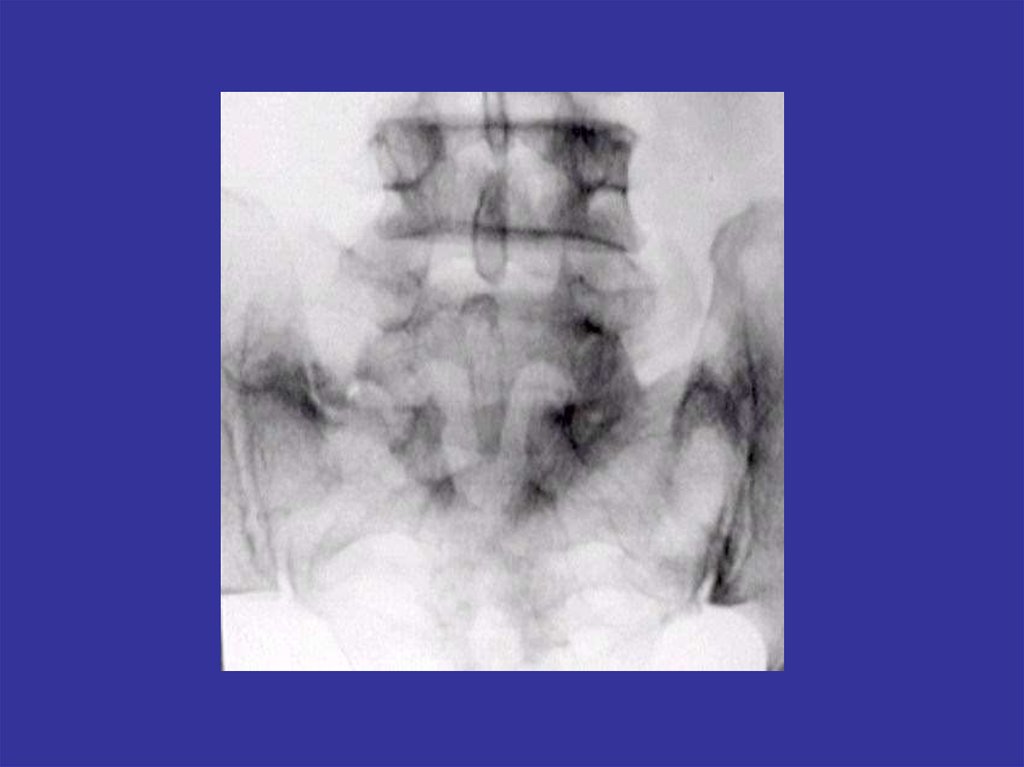

Аномалии развития позвоночника